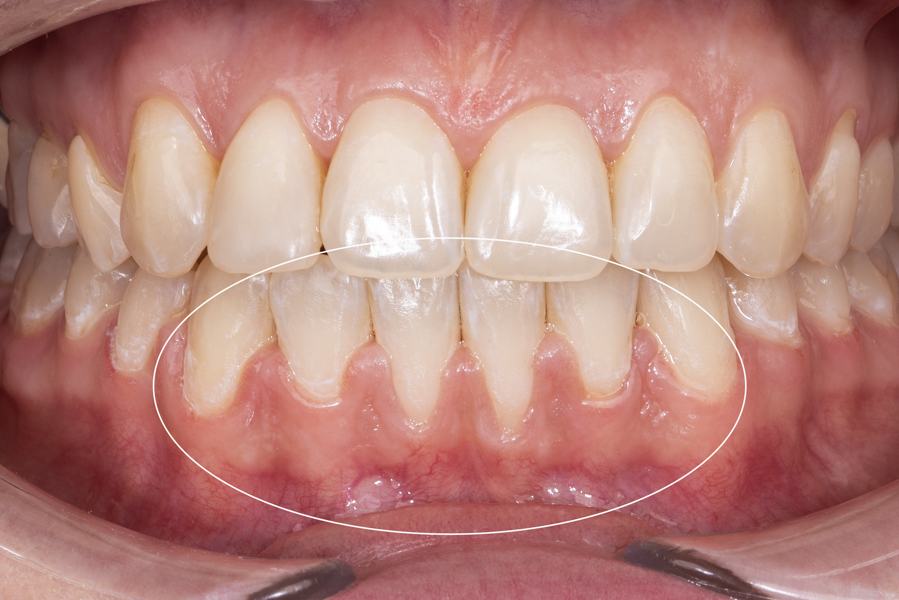

Recesja dziąsła (inaczej zanik lub cofanie się dziąseł) to proces, który odsłania korzenie zębowe, a co za tym idzie, może powodować nadwrażliwość zębów, próchnicę oraz defekt estetyczny podczas mówienia i uśmiechu.  Wśród przyczyn recesji dziąsła można wymienić m.in.: wady zgryzu, genetyczną budowę dziąseł, chorobę okluzji (bruksizm) oraz nieumiejętne szczotkowanie zębów i nieprawidłową higienę.

W SOBOTA House Of Dentistry proces leczenia recesji dziąseł poprzedzony jest zawsze wizytą ogólną i bardzo dokładną diagnozą, mającą na celu ustalenie przyczyny problemu. W zależności od źródła recesji, wybieramy odpowiednią metodę leczenia. Recesję przykrywamy własnym dziąsłem Pacjenta. Zabieg jest bardzo skuteczny, miejsce przykrycia recesji szybko się goi i nie sprawia Pacjentowi dyskomfortu.

Zabiegi wykonywane są w znieczuleniu komputerowym. Podczas leczenia korzystamy wyłącznie ze sprawdzonych metod, a stosowane techniki i narzędzia mikrochirurgiczne pozwalają na atraumatyczne postępowanie z delikatnymi tkankami przyzębia.

Wszystkie zabiegi wykonywane są przez specjalistę, jednego z najlepszych stomatologów-chirurgów w Polsce, który zajmuje się leczeniem recesji dziąsłowych od wielu lat. Przeprowadził wiele skutecznych zabiegów odbudowujących prawidłową linię dziąseł, przywracając w ten sposób Pacjentom pewność uśmiechu.